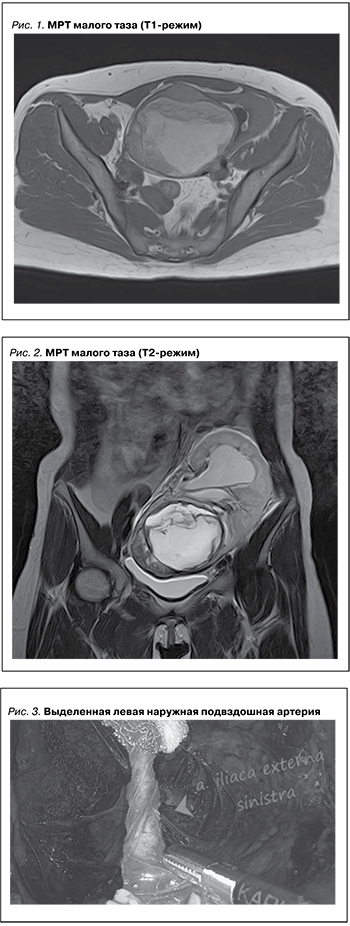

У пациентки 33 лет при УЗИ выявлена опухоль трансплантированной почки, подтвержденная данными магнитно-резонансной томографии – МРТ (рис. 1, 2), размеры образования составили 10,3×8,3 см, тазовой лимфаденопатии не было.